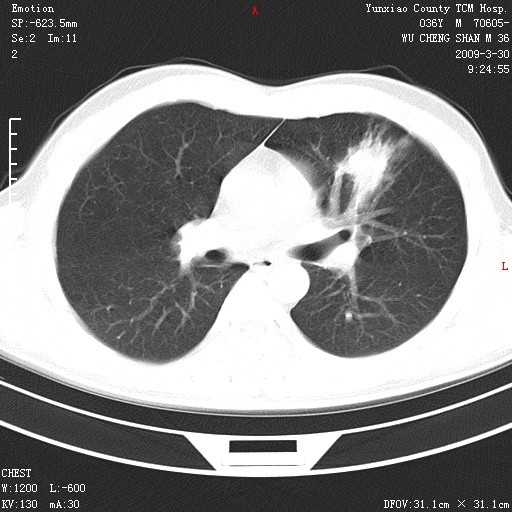

本院家属,胸痛,无咳嗽咳痰发烧病史,治疗一个月后病灶无明显改变,支气管镜示左肺慢性炎症,未见癌细胞,

胸痛,无咳嗽咳痰发烧病史,治疗一个月后病灶无明显改变,支气管镜示左肺慢性炎症,未见癌细胞,左肺下叶前段片状影,边缘不清,内见空支气管征,纵隔未见淋巴结肿大,周围无卫星灶,应考虑为炎性病变。

胸痛,无咳嗽咳痰发烧病史,治疗一个月后病灶无明显改变,支气管镜示左肺慢性炎症,未见癌细胞,左肺舌叶片状影,边缘不清,内见空支气管征,周围无卫星灶,应考虑为炎性病变。

左肺舌叶片状影,边缘不清,内见空支气管征,炎性病变